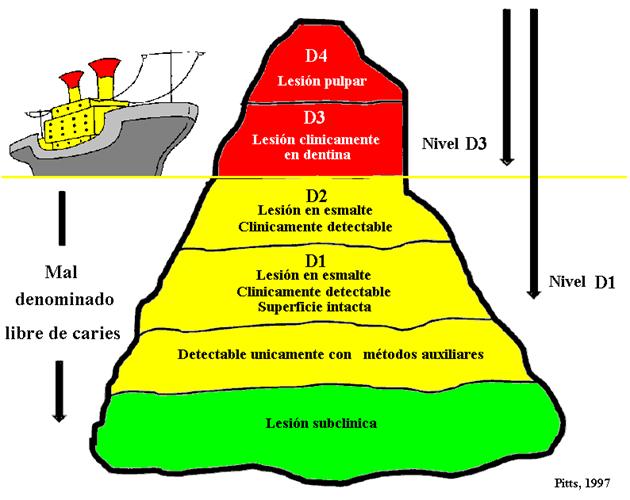

Nivel de

detección de caries: Témpano de Pitts |

|

|